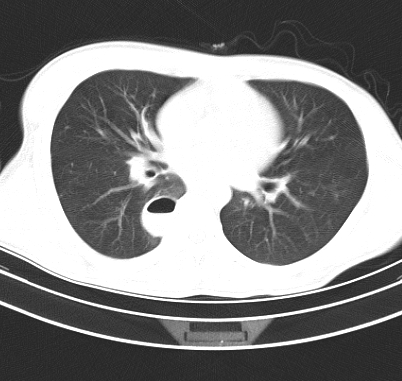

标题: CT19170:男 24岁,胸部外伤一周行CT检查 [打印本页]

男 24岁,胸部外伤一周行ct检查 未传纵隔窗

结合病史考虑肺挫伤后所致的肺气囊表现

结合临床考虑为右肺下叶背段撕裂伤。

首先考虑肺裂伤形成的液气囊肿.纵膈胸膜包裹性的液气胸可能性小,病变主要在肺内.

支持外伤性肺气囊。

肺撕裂伤液气囊形成

考虑外伤肺撕裂致右肺下叶纵隔胸膜下液气囊肿。

壁光滑完整,周围未见炎性灶及粘连带,考虑肺囊肿,不一定跟外伤有关!

结合临床考虑为右肺下叶背段撕裂伤后形成局限性包裹性的液气胸。

有否先天性可能,病程仅一周,病灶周围实质无明显异常表现.